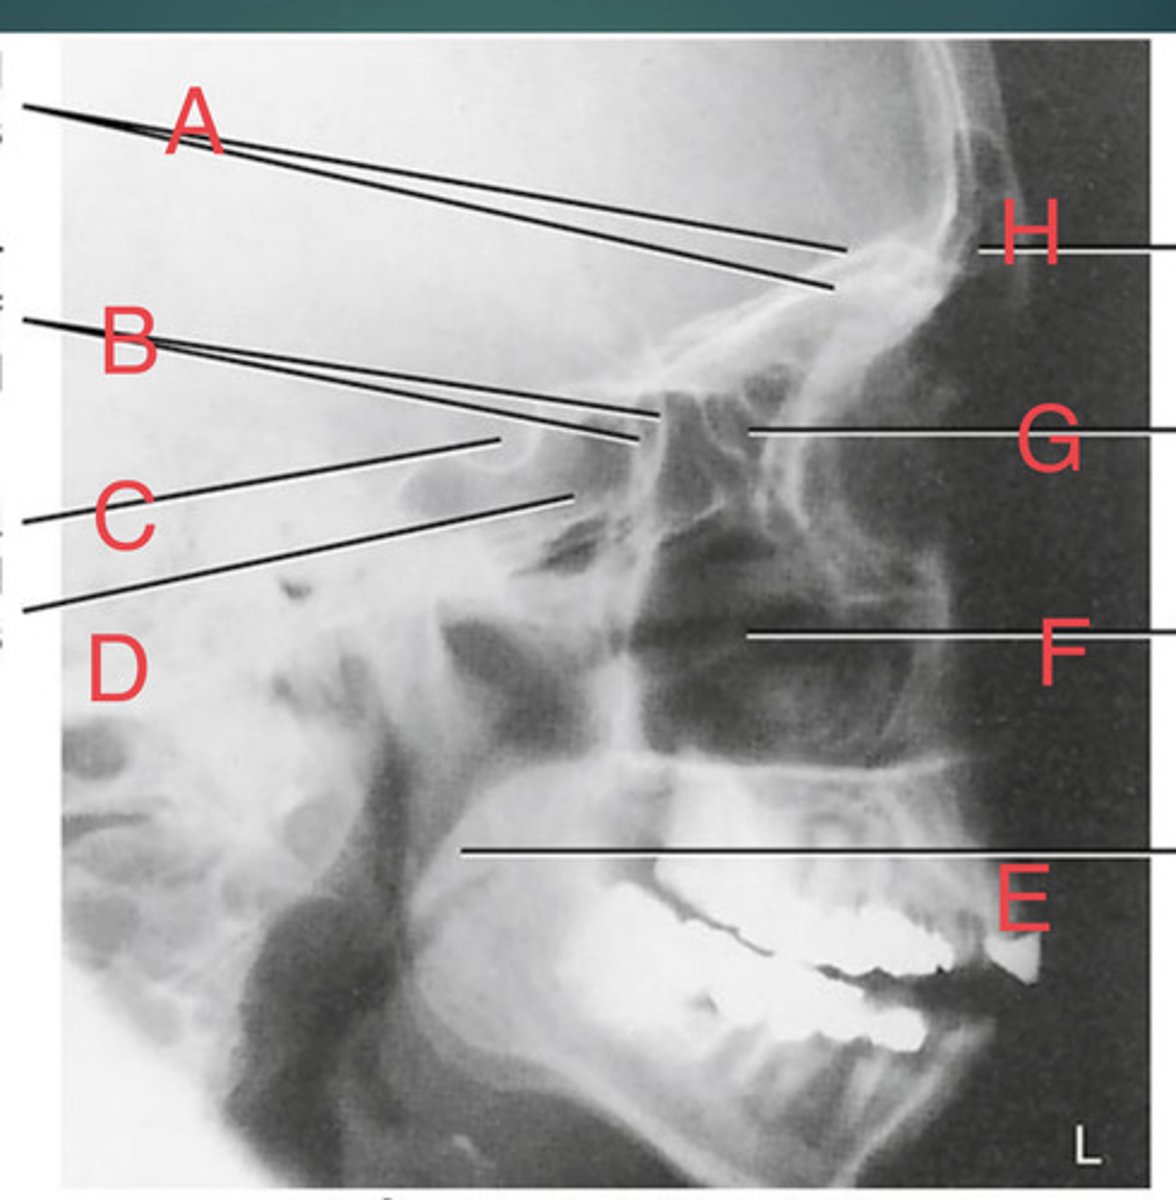

Lateral sinus

What position?

L. Orbital roofs

A.

L. Greater wings of sphenoid

B.

sella turcica of sphenoid

C.

L. Sphenoid sinus

D.

L. Rami of mandible

E.

L. Maxillary sinuses

F.

L. Ethmoid sinuses

G.

L. Frontal sinuses of frontal bone

H.